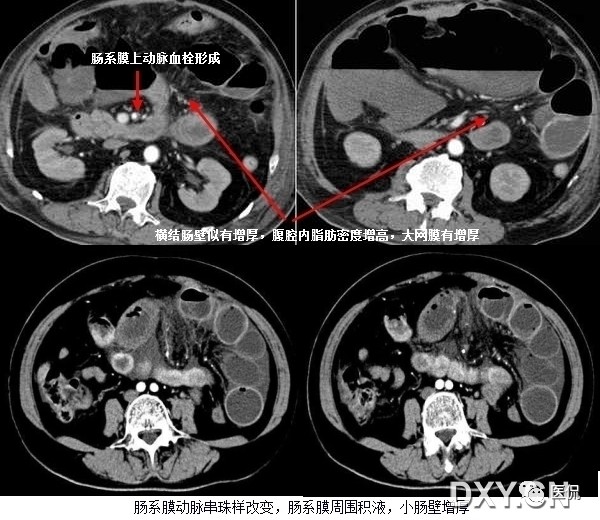

25 肠系膜混浊征

肠系膜脂肪受炎症细胞、液体(水肿、淋巴液和血液)、肿瘤浸润及纤维化的CT表现。当肠系膜被液体或细胞浸润时,其脂肪CT值增加到-40~ -60HU(肠系膜脂肪的CT值类似于皮下及腹膜后脂肪,约-100~-160hu,肠系膜血管常呈横行或断面显示。),动、静脉失去锐利边缘。根据浸润的性质和范围,肠系膜血管可部分或完全模糊,顺着脏层腹膜常能发现肠系膜疾病的线索,在周围脂肪衬托下,肠系膜病变显示更加清晰。

上两幅图:肠系膜上动脉栓塞

下两幅图:十二指肠扭转致肠壁增厚、肠系膜水肿

造成肠系膜混浊征的主要有以下疾病需要鉴别:

1)肠系膜水肿

肠系膜水可由许多疾病引起,如低蛋白血症、肝硬化、肾病、心力衰竭、三尖瓣狭窄病变、缩窄性心包炎、门脉高压、门静脉血栓、肠系膜血管栓塞、血管炎、柏-查综合症、下腔静脉阻塞和外伤等,如肠系膜水肿是由全身性疾病引起,则有广泛的皮下水肿和覆水。CT扫描常由于身体近床侧的皮下组织内有新月状高密度影,代表增多的细胞外水分,肠系膜呈云雾状改变的范围从肠管的浆膜面直到肠系膜上动、静脉起始部的肠系膜根部;肝硬化由于低蛋白血症门脉高压常引起肠系膜水肿。肠系膜动、静脉血栓所引起的肠系膜水肿可呈局限性或弥漫性,发现血管内栓子或管腔缩小常可提示肠系膜血管栓塞,肠缺血的其他征象为节段性肠壁增厚,气肿性肠炎,当出现坏死时可有小静脉分支内集气。